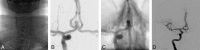

Fig 2.

A middle-aged patient presenting with a ruptured aneurysm of the anterior communicating artery (measuring 7 × 4 mm), treated using coiling via left TRA. A, The right common carotid artery was catheterized using a Simmons shaped catheter via left TRA; then, a guiding catheter (B) was advanced over it. C, An angiogram of the right ICA highlights the irregular aneurysm of the anterior communicating artery. D, An angiogram of the right ICA shows the total occlusion of the aneurysm.